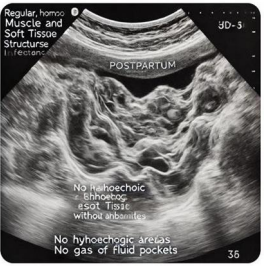

Figure 2